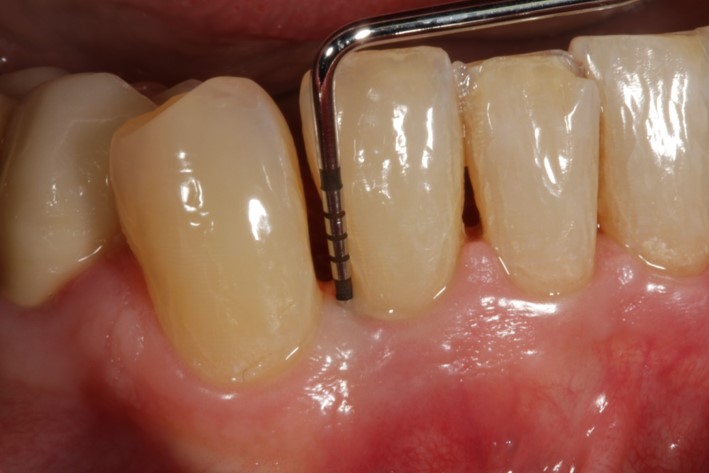

02/08 - Pre-surgical probing reveals a deep intrabony defect on the distal aspect of tooth 42.

Non-contained intrabony defect treated using Straumann® Emdogain® and a synthetic bone grafting material - Prof. Dr. Dr. A. Kasaj